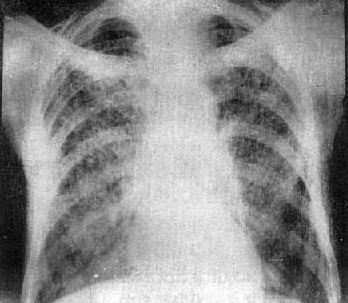

近年来,肺结节的发病率越来越高。我们经常能看到或听到周围的亲友,体检时发现肺结节。造成这种情况的原因,一方面是现代人生活节奏快、工作压力大、生活习惯差、空气污染等,导致肺结节的发病率较以前有所上升。另一方面,过去在常规体检中,胸部X光片用于确定肺部状况。

然而,软组织的X射线分辨率不是很高,小于1厘米的结节很难发现。现在,越来越多的人选择胸部CT进行体检。这样,随着医学影像诊断技术的进步,也可以发现和检测2-3mm的肺结节。因此,总的来说,肺结节的检出率越来越高。